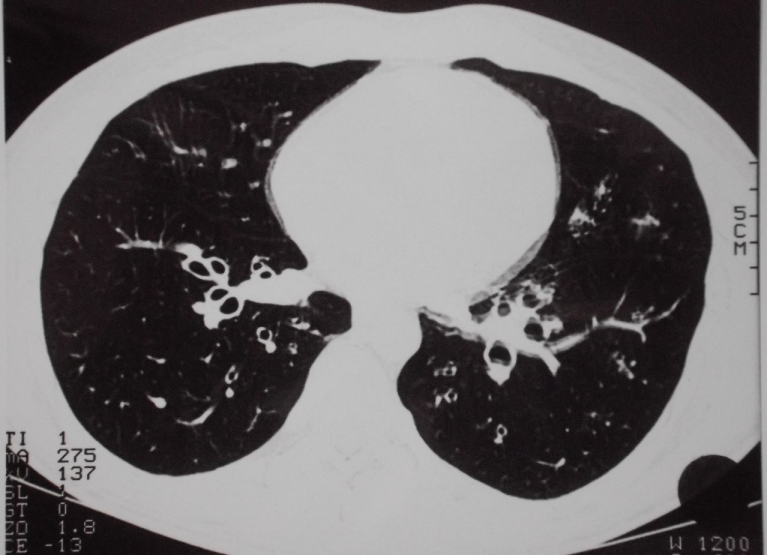

A non-smoking 22-year-old male patient reported strong bronchitic complaints, permanent cough, massive purulent expectoration and dyspnoea during exercise for two years before visiting the hospital. He had infrequently bloody stool, but unfortunately this symptom was overlooked at first consultation. Lung function was borderline normal, but pO2 was only 75.5 mmHg. There were no signs of immunologic disorders or allergy. HR-CT presented thick bronchial walls and tubular bronchiectasis (Figure 1 [Fig. 1]). Bronchoscopically a massive suppurative bronchitis with mucoid impaction was seen, but bacteriological and virus findings were negative. Indication of cystic fibrosis or bronchopulmonary aspergillosis was not seen. Histology is shown in Figure 2 [Fig. 2]. The patient was successfully treated with antibiotics and steroids and he became slowly but continously better. A bronchoscopic control half a year later showed a macroscopically and histologically unchanged situation. At that time he developed abdominal complaints with bloody diarrhoea. Colonoscopy showed macroscopically UC, histologically confirmed (Figure 3 [Fig. 3]). The treatment led to clinical improvement of the abdominal and bronchial complaints. Nevertheless 15 months later bronchitis and colitis were still present if analysed endoscopically although clinically silent.

A very characteristic finding in patients with UC is bronchiectasis, which can be diagnosed clinically by mass sputum expectoration or by X-ray, today mainly by CT [1], [2], [4], [5], [6], [8], [19]. Using HRCT, Mahadeva found 13 out of 14 patients with UC to have bronchiectasis [15]. With these data it is obvious that a particular relation exists between bronchitis and colitis in form of a distinct syndrome. The bronchial involvement can take place before the clinical outbreak of UC, but mostly thereafter, with or without a corresponding clinical activity of UC. Therapeutic interventions as IBD modifying drugs or colectomy have no controlling effect of the respiratory manifestations [9], [32], but it is reported that the bronchial alterations respond to corticosteroids [36], as holds true also in our case.

The bronchial changes in UC are often reported as necrotising. It is not known, whether the morphological changes in bronchial and colonic tissue are part of a common process. Today it is too early to answer this question. We would not speculate on common pathogenetic mechanisms, although some authors discuss a common inflammatory vulnerability [24] or pulmonary-intestinal mucosal inflammatory cross-talk [37] involving multiple pathogenetic pathways including microbiomics [4]. The accentuated suppurative character of the bronchitis in many of the patients with UC is striking. Massive mucopurulent secretions and frequently a development of cylindrical bronchiectasis as a result of destruction of bronchial wall may show similarities with the changes in the colonic mucosa (Figure 2 [Fig. 2] and Figure 3 [Fig. 3]). Though changes in the bronchial structure can be easily discovered with lung CT [15], [19], [27] unfortunatly this is only seldom performed in patients with UC. There is no systematic prospective study addressing this clinical problem.